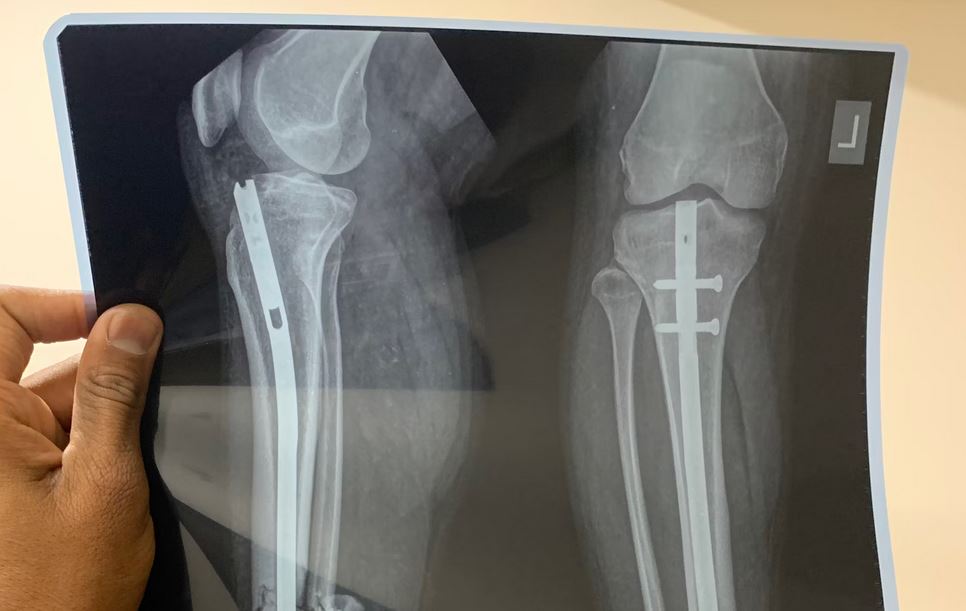

We mean evidence like surgery notes, diagnosis reports, imaging results, physical therapy records, even your personal pain journal if you’ve been keeping one.